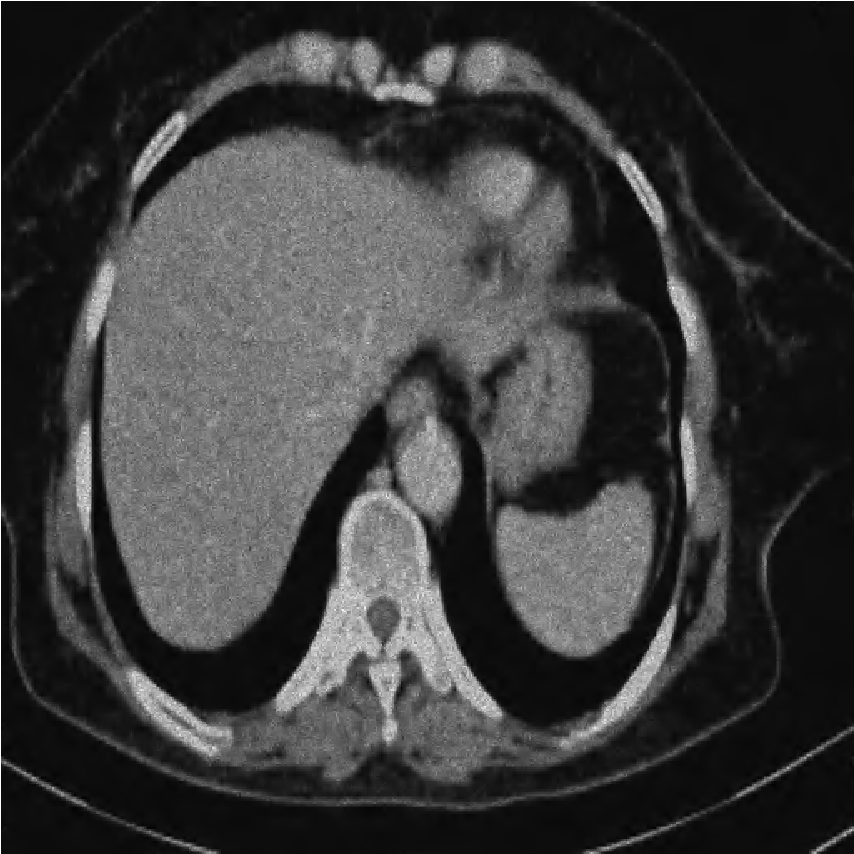

We performed extensive numerical simulations to examine the performance of the aforementioned denoising methods. For this purpose, we used a pixel grayscale CT scan image, shown in Fig. 2a. Noisy versions of this image were created by adding different types of noise at various strengths. The noise types considered are Gaussian noise, uniform noise, salt and pepper noise, and Poisson noise. The following subsections present and explore the results obtained from the various denoising methods. All computational programming were carried out using Mathematica 12.0.

[b)Gaussian]

[c)Uniform]

[d)Poisson]

[e)Salt Pepper]

Contrary to the initial hypothesis that DWT’s multi-resolution and spatio-frequency localization would grant it superior denoising capabilities [9, 11], our results unequivocally demonstrate that the block-based DFCT approach achieved significantly higher SNR, PSNR, and lower IM values for all tested noise types (Gaussian, Uniform, Poisson, Salt-and-Pepper). Fig. 7 shows the values of PSNR for both motheds for comprision.

This finding highlights a critical principle in image processing: the implementation strategy (global vs. local processing) can be as important as the choice of transform itself. Future work could explore local or adaptive wavelet thresholding schemes (e.g., context modeling, spatially varying thresholds) to leverage the strengths of wavelets while incorporating the local adaptability that made DFCT successful in this study. Figs. 8-11 show visual comparison of denoising results for the four kinds of noise. In the Figs. 8-11 the left image is noisy input image, the middle image is denoised image using the best wavelet method (BIOS wavelet with Hyperbola threshold for case of Gaussian and uniform noise, BIOS wavelet for Poisson noise and Daubechies wavelet with SURELevel for salt-and-pepper noise) and, the right image is denoised using DFCT.